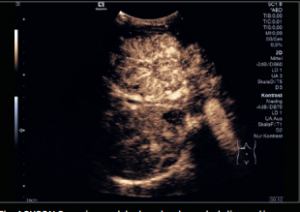

The Departments of Medical Physics and Radiology at the University of Wisconsin School of Medicine and Public Health provide a rich environment for performing research in Ultrasound Imaging (US). The infrastructure includes a wealth of equipment, support staff, and researchers with clinical and technical expertise. Please see below for a brief overview of the US equipment, personnel, and areas of ongoing research. You can also follow the links to see more information about the research program, or to apply for time on the US systems to conduct your own research project.

Housed within WIMR is a core group of investigators specializing in US research. This is a multi-disciplinary group, composed of faculty, post-docs, and students from the Departments of Medical Physics, Biomedical Engineering, Mechanical Engineering, Radiology, and others. The main emphasis of the research is developing new acquisition and analysis methods for enhancing the capabilities of clinical US imaging. Current projects focus on shear wave elastography, investigations of the underlying collagen microstructure of tissues, breast elastography, multi-scale/multi-modality imaging, platelet rich plasma injections and many other topics.

US research is performed by a number of investigators beyond the core group as well. Within the University of Wisconsin and throughout UW Health, there is a long-standing tradition of inter-departmental and inter-disciplinary collaborations that are necessary for advancing clinical and basic science. We work within multiple different project areas including Neurosurgery, OB, Orthopedics, Sports Medicine, Nephrology, the Laboratory for Optical and Computational Instrumentation, and many others.